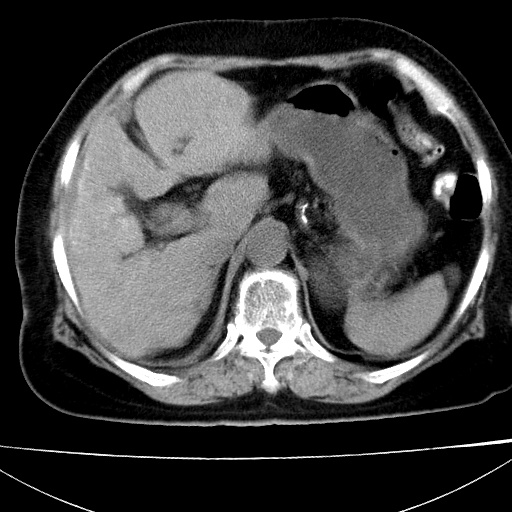

胆囊增大饱满,壁增厚。胆囊颈部见软组织密度影。临近肝右叶前段见片状低密度区,病灶下部见条状钙化,少量胸腹腔积液。意见:胆囊颈癌累及肝脏。

病人以胆囊癌手术的,病理结果为中分化腺癌。

现在看看肝右叶内圆形低密度影你们考虑什么呢?

肝内圆形低密度影考虑扩张的胆管

请看3mm重建像如下: